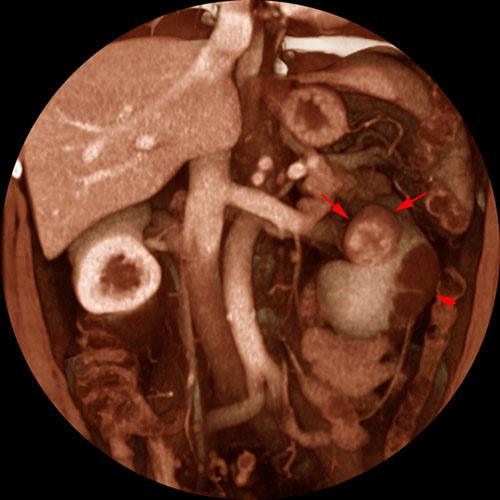

Quiste renal hemorrágico